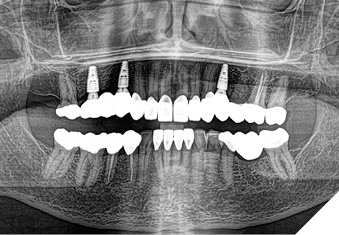

Articulated diagnostic casts showed very limited to no overjet and 90% of overbite. The wear pattern on the palatal aspect of her maxillary teeth appeared to be secondary to her tight occlusion since mandibular anterior teeth were in close contact with these surfaces with no “room” for protrusive movements. The diagnosis for this patient was: partial edentulism, failing existing restorations and attrition and abfraction secondary to parafunction. We discussed different options, including orthodontics in order to increase her overjet so we could have prosthetic space to restore her worn down teeth. We also discussed tooth replacement options. After a second consultation appointment which she attended with her husband, she decided that she did not want to replace her teeth with removable prosthetics. She also declined referral to an orthodontist. After discussion of multiple options of treatment to address all her chief complaints, her treatment consisted of a full mouth reconstruction with full coverage restorations in Zirconia for teeth 11-13,17,22-23,25-27,32-42, 44-47 and partial coverage restorations with lithium disilicate restoration for teeth 33,34 and 43. Replacement of teeth was achieved with a fixed partial denture to replace tooth 36 and a 3-unit implant supported bridge to replace teeth 24-26. In terms of occlusion, we created a more favorable occlusion with a proper anterior guidance, canine disclusion with more freedom for protrusive movements, which hopefully would decrease the parafunction, and alleviate some of her muscle pain. Before completing the case, the patient spent several weeks with provisional restorations which reflected the increase in vertical dimension of occlusion and the new occlusal scheme. During this trial phase, we assessed comfort, esthetics, function, decrease in pain and speech (Figs. 12-17).

Fig. 12

Fig. 13

Fig. 14

Fig. 15

Fig. 16

Fig. 17

During a 6 month follow up visit, the patient presented with reduced pain in her masticatory muscles and no sensitivity on her teeth. She was also pleased that her chewing function had improved and she loved her brighter smile. She used her night guard every night. She is in a 6-month recall protocol to ensure all restorations are in proper condition and that her occlusion continues to be ideal. We also monitor the health of the soft tissues and peri-implant health.